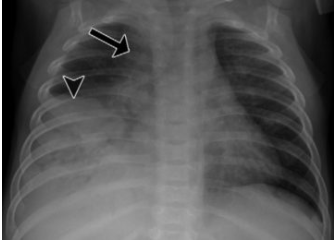

Q

o que é visto nesse raio-x

A

Linfonodomegalia mediastinal (seta) e consolidação nos lobos médio e inferior direito (cabeça de seta)